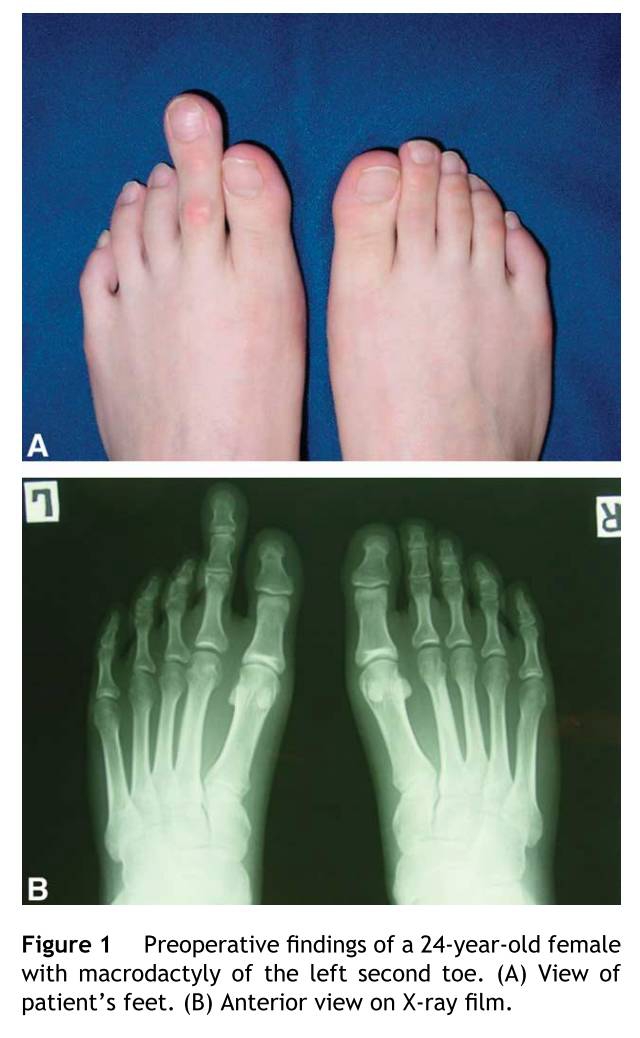

24岁的女性患者左足第二趾巨趾畸形。父母发现在3岁的时候第二趾和其他趾体生长速度不一样,但是没有接受任何治疗。父母主诉外形不美观的痛苦大于功能。患者行走和跑步没有问题。其他么有合并畸形。在趾甲的部位测量,比正常的足趾长15毫米和厚15毫米。患趾功能和感觉正常。拍片显示跖骨和趾骨增大。近节趾骨7毫米,中节趾骨5毫米,末节趾骨4毫米,同对侧比跖骨长4毫米。其余趾体同对侧大小一样。